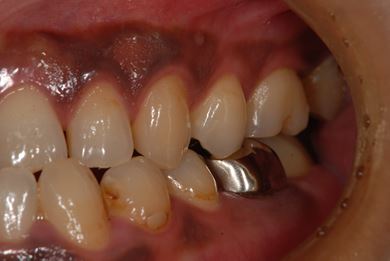

治療前

• 治療前